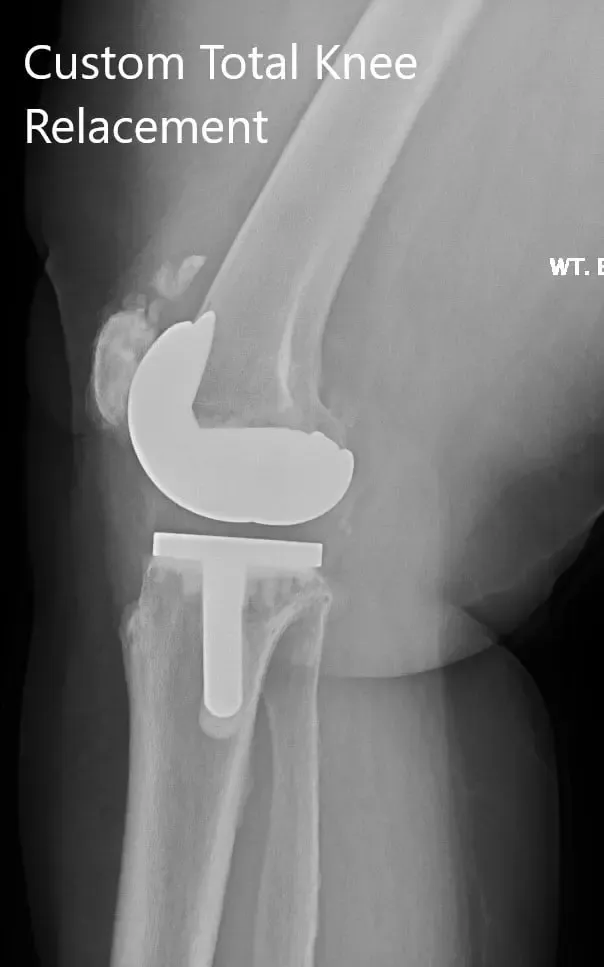

Postoperative X-ray showing the lateral views of both knees.